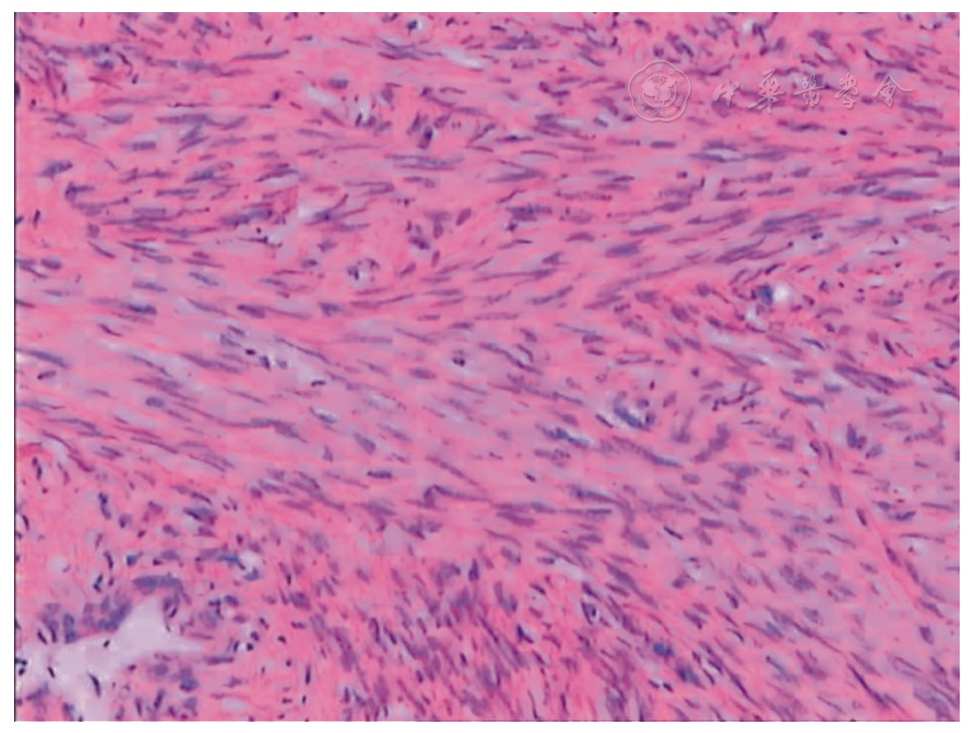

图1 普通子宫平滑肌瘤

图2 血管性平滑肌瘤

图3 子宫静脉内平滑肌瘤

图4 伴出血的平滑肌瘤

图5 间质细胞肉瘤